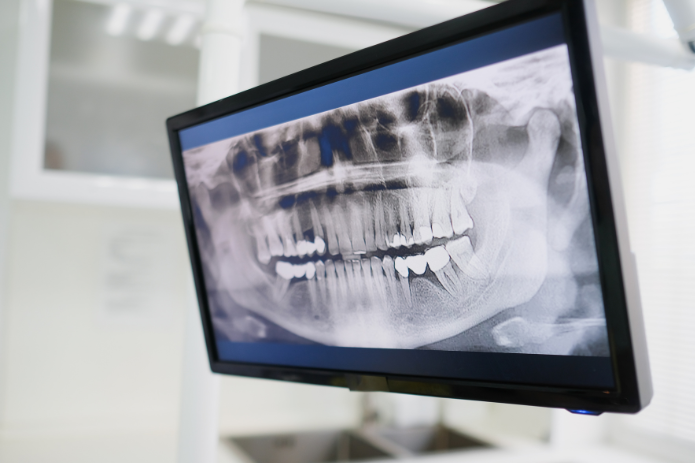

A panorámaröntgen, más néven orthopantomogram, egy olyan röntgenfelvétel, amely az egész fogsort, az állkapcsot és a környező csontokat egyetlen képen mutatja meg. Képet ad az alsó és felső fogsorról, beleértve a bölcsességfogakat, az állkapocsízületeket és a szájüreg körüli struktúrákat. Az ilyen típusú röntgenfelvétel lehetővé teszi a fogorvos számára, hogy gyorsan és átfogó képet kapjon a páciens szájüregi állapotáról. A panorámaröntgen képes észlelni olyan problémákat, amelyeket a hagyományos, kisebb fókuszú röntgenek nem mutatnak meg. Non- invazív, fájdalommentes eljárás, amely nem igényel semmilyen invazív beavatkozást.

Mit mutat meg a fogorvosnak a panorámaröntgen?

• A fogak elhelyezkedése és fejlődése

• A gyökérhártya állapota

• Állkapocsízületi problémák

• A csontszerkezet egészsége

• Fogászati implantációk tervezése